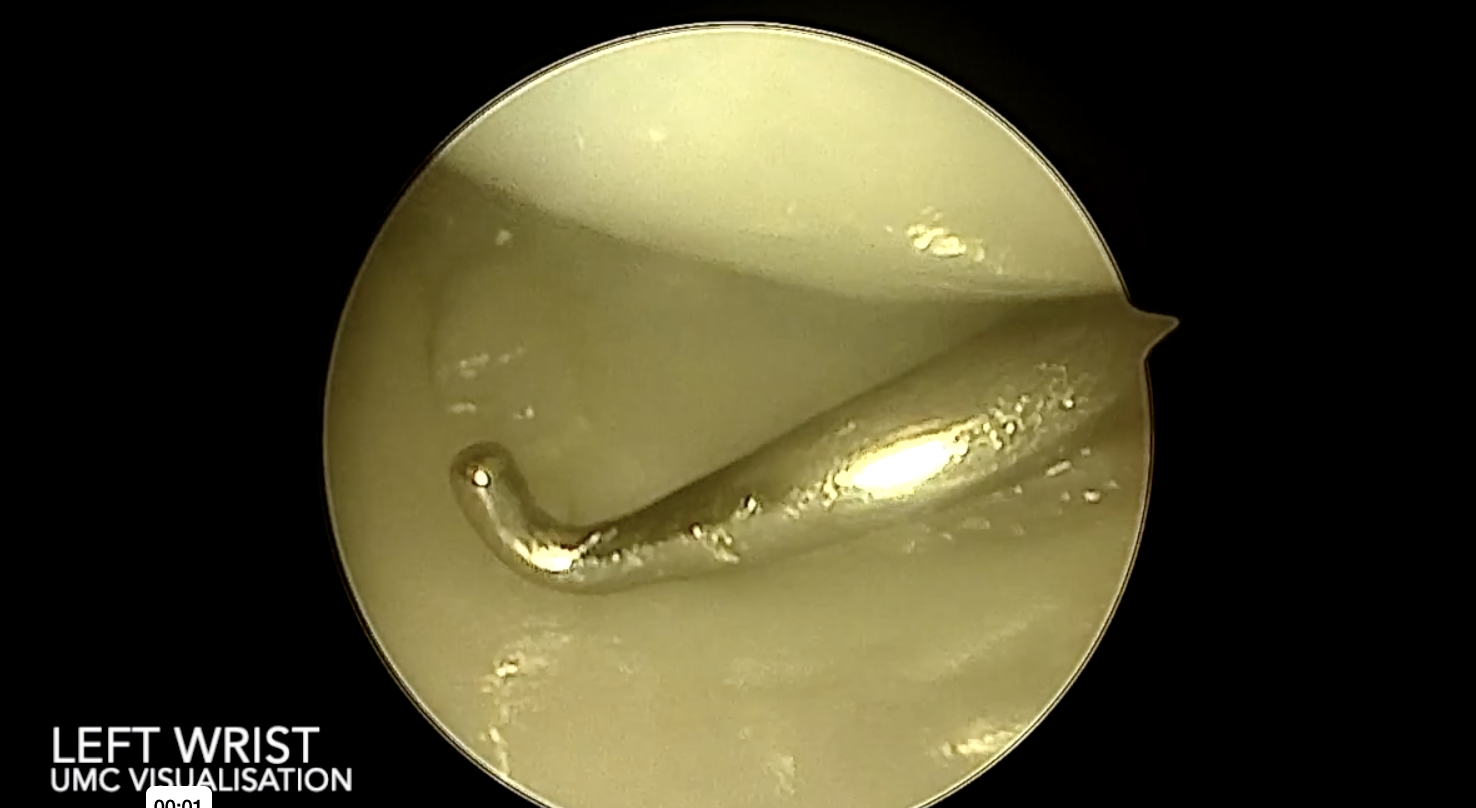

SOULS Research is currently conducting a study investigating the reliability of the EWAS classification of scapholunate ligament injuries. Given your expertise, we ask that you consider participating in the study. Participation would involve viewing, and grading, a number of intra-operative videos using a standardised grading system.

A copy of the classification system is presented below.